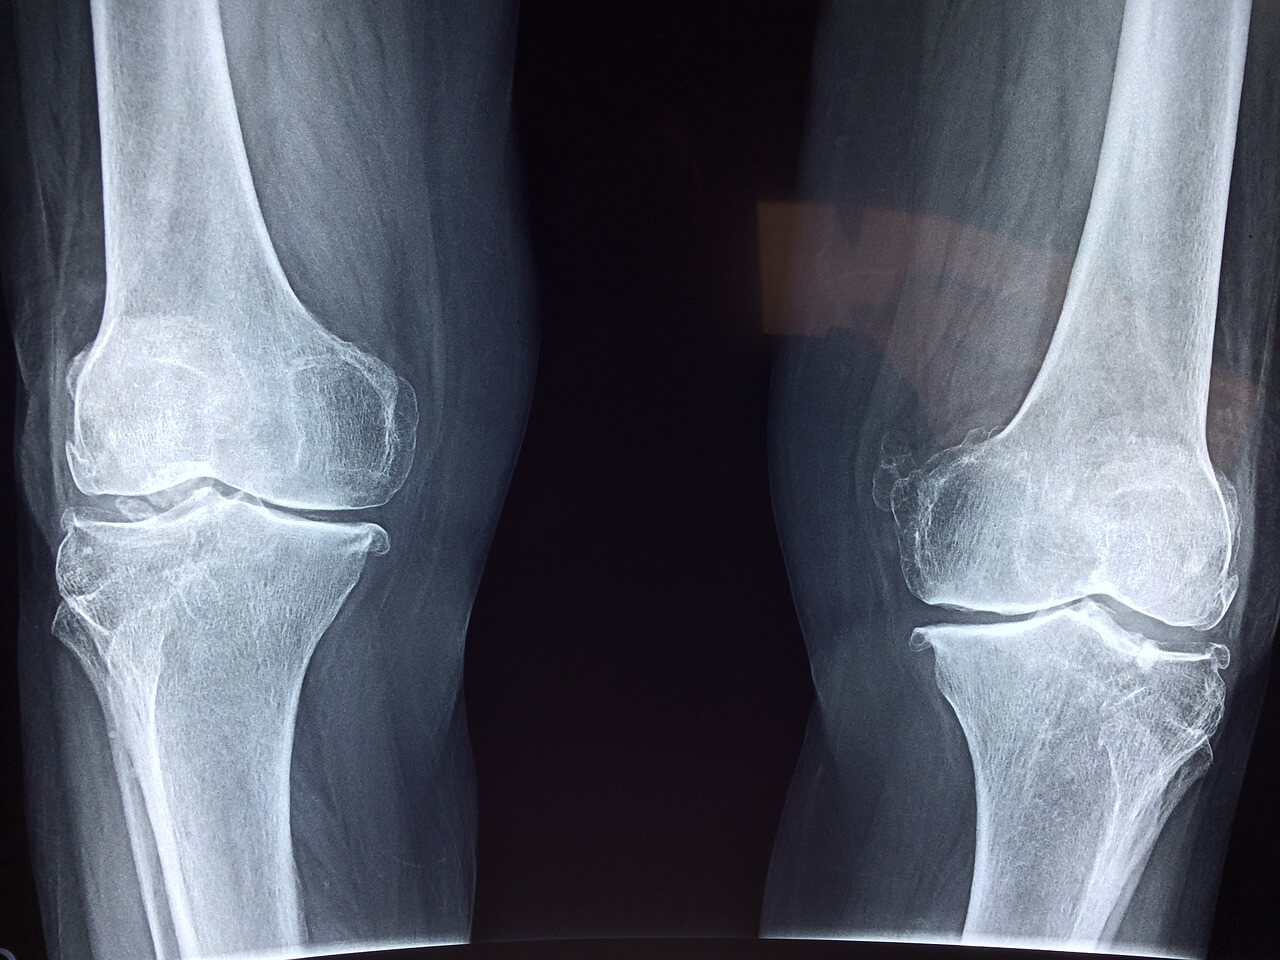

3️⃣ 병원에 따라 차이가 있는 이유

✅ 무릎인공관절 로봇수술 비용은 병원마다 왜 이렇게 차이가 나는 걸까요? 그 이유는 아래와 같은 요소들 때문이에요.

● 로봇 장비 도입 여부와 종류 최신 로봇 수술 장비(예: 마코 스마트로보틱스 등)를 사용하는 병원은 기기 유지비나 정밀도 측면에서 가격이 더 높게 책정될 수 있어요.

● 지역 차이 서울 대형 대학병원과 지방 중소병원의 가격 차이도 존재해요. 지방은 다소 저렴할 수 있지만, 로봇장비 보유 병원이 적을 수 있어요.

✅ 실제로 어떤 병원은 로봇수술 추가비용이 150만 원 이하로 안내되기도 하고, 어떤 곳은 300만 원 이상 청구되기도 해요. 정보는 투명하게, 결정은 신중하게 하시는 게 가장 좋아요.